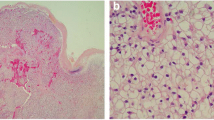

The isolated specimen showed a pedunculated tumor in the fundus of the gallbladder, and the surface of the tumor appeared black as a result of bleeding (Fig. 3a). Microscopically, we observed prominent vascular proliferation in the stalk and basal part of the tumor (Fig. 3b). The tumor was hypercellular and composed of clear cells arranged in funicular or alveolar growth with vascular interstitial tissue (Fig. 3c). The surface of the tumor was covered by epithelium, and extensive hemorrhage was observed under the surface (Fig. 3b). These histopathologic characteristics coincided with those of the renal tumor resected 15 years earlier (Fig. 3d, e).

The surgical specimen shows a black pedunculated tumor in the fundus of the gallbladder (a white arrow). Pathological examination of hematoxylin and eosin staining shows tumor cells with clear cellular cytoplasm growth (b ×20, c ×200), and it is similar to the features of the renal primary tumor (d ×20, e ×200)

We performed immunohistochemical staining for vimentin and cytokeratin 7 (CK7). The tumor stained strongly for vimentin, but staining for CK7 was almost negative (Fig. 4), although for CK7, we observed a partially nonspecific immune reaction due to use of an automated immunostainer. These pathological features were similar to those of the renal primary tumor. Therefore, we diagnosed the gallbladder tumor as a metastasis from renal cell carcinoma. Our patient’s postoperative course was uneventful and she was discharged at postoperative day 5. She is alive and recurrence free 3 years after cholecystectomy.

For an adequate follow-up and informed decisions about adjuvant immunotherapy with interleukin-2 and interferon alpha after cholecystectomy, gallbladder metastasis of RCC should be differentiated from primary clear cell carcinoma of the gallbladder through histochemical examination. Immunohistochemically, primary clear cell carcinoma of the gallbladder is strongly positive for CK7 but negative for vimentin, and metastatic RCC of the gallbladder is positive for vimentin but negative for CK7 [17]. Based on the immunohistochemical findings, our final diagnosis was metastatic gallbladder tumor from RCC as opposed to primary clear cell carcinoma of the gallbladder.